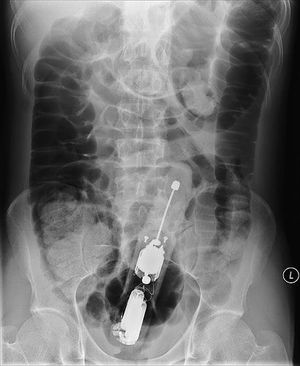

A man came to the ER with a foreign body in his rectum. He explained that he had constipation for many days before he came up with this "method" to try to fix it. The majority of cases of rectal foreign bodies are the result of insertion during erotic activity. Typically found objects are vibrators, dildos, light bulbs, candles, shot glasses, and bottles. Some rectal foreign bodies may have been initially swallowed but later present with complications in the rectum. Patients may be very embarrassed to disclose the circumstances regarding the foreign body insertion, and there may have been multiple attempts at self-removal. Typical clinical findings of a rectal foreign body are pain with defecation, abdominal pain, rectal bleeding, pruritus, and constipation. Delays in seeking medical attention and multiple attempts at self-removal can lead to mucosal edema and muscular spasms, making removal of the object more difficult.